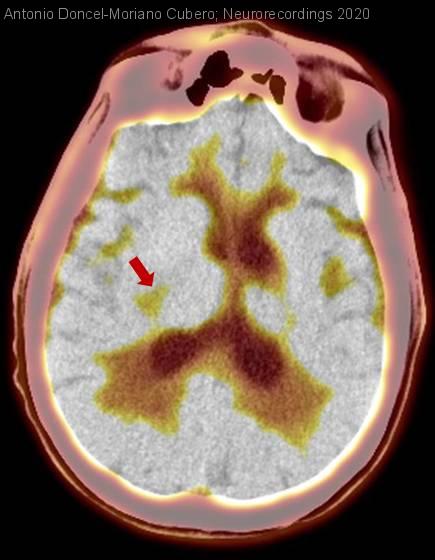

Diagnóstico final: Recidiva de linfoma cerebral primario

Varón de 54 años con antecedentes de linfoma primario del sistema nervioso central de células grandes diagnosticado en 2010 por alteración conductual y deterioro cognitivo rápidamente progresivo. Recibió quimioterapia (carmustina, metotrexato y Ara-C: esquema BAM,...